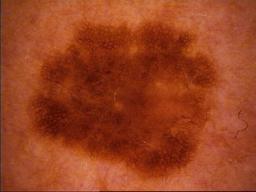

Test set from the ISIC 2018 Challenge. The lesion images come from the HAM10000 Dataset, and were acquired with a variety of dermatoscope types, from all anatomic sites (excluding mucosa and nails), from a historical sample of patients presented for skin cancer screening, from several different institutions. Images were collected with approval of the Ethics Review Committee of University of Queensland (Protocol-No. 2017001223) and Medical University of Vienna (Protocol-No. 1804/2017).

The distribution of disease states represent a modified "real world" setting whereby there are more benign lesions than malignant lesions, but an over-representation of malignancies.